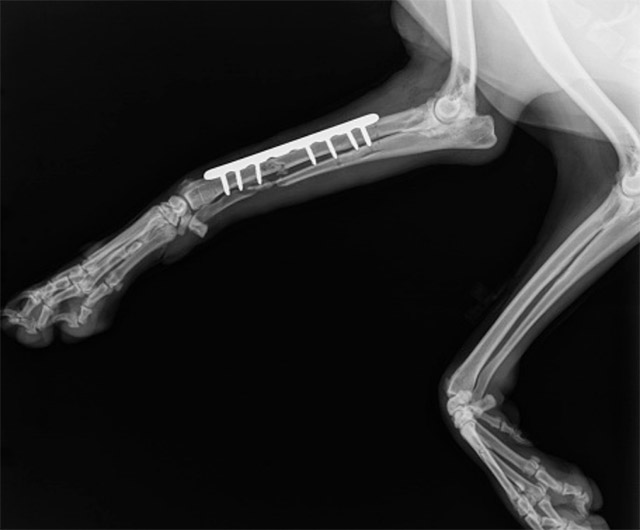

LCPシステム 小型犬の骨折に新しい治療

小型犬はソファや階段でジャンプした時やフローリングで足を滑らせて転んだ時に、骨折してしまうことがあります。骨が小さくもろい小型犬の骨折治療は比較的難易度の高い手術です。

当院ではSYNTHES社が開発した『LCP(Locking Compression Plate)システム』を導入しています。従来のプレートにある問題点を克服し、骨折治療に伴う合併症(骨癒合不全・ストレスシールディング・再骨折)リスクを低減できる新しい治療法です。

中型犬以上、猫にも適用することができます。

ポメラニアン、チワワ、マルチーズ、イタリアングレーハウンド